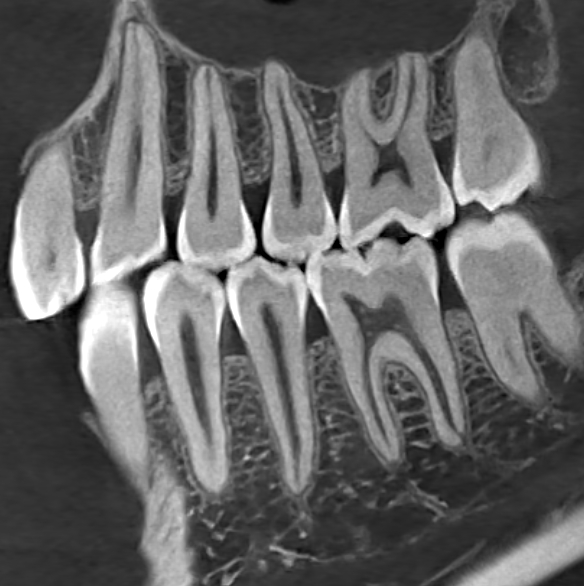

Pirox-A 超清影像

高空间分辨率的CT影像,能更清晰显示牙周膜牙槽神经的组织结构细节。高空间分辨率对三维体模的构建、微小结构的分析、手术路径的规划都意义重大。